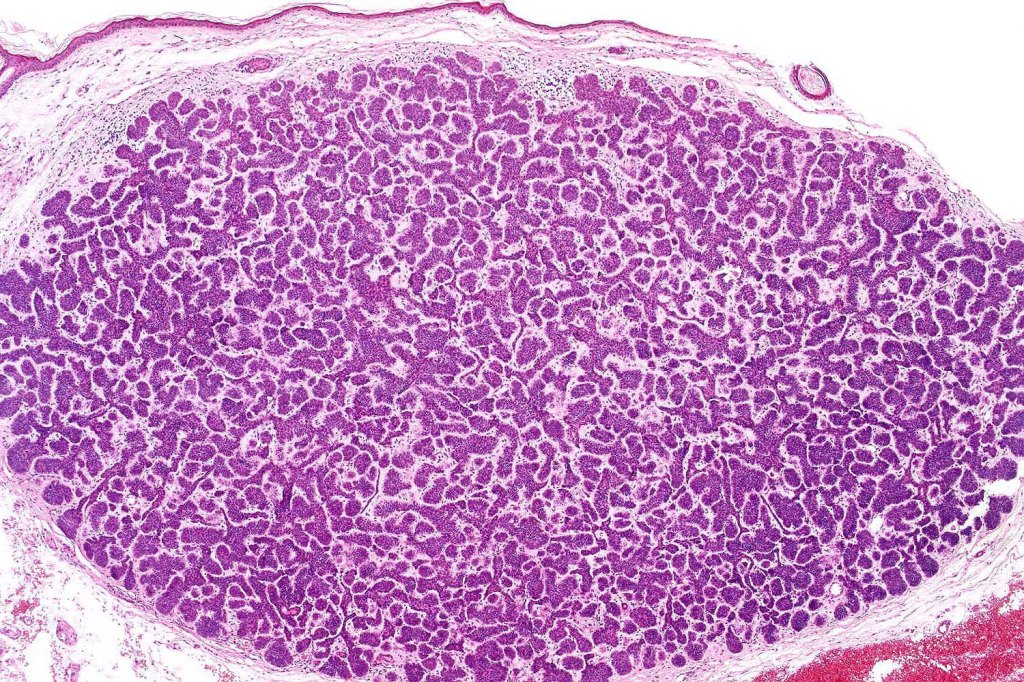

Histological features

•The classical appearance consists of keratocysts & lobules of basaloid cells

•Some tumors are devoid of keratocysts

•Variable continuity with the epidermis

•Basaloid lobules show peripheral palisading

•Retraction artifact and mucin deposition as seen in BCC are not present

•Perifollicular mesenchyme is always conspicuous and sometimes densely aggregated are seen indenting the baslaloid lobules (papillary mesenchymal bodies)

•Narrow epithelial strands arising from the basaloid lobules are often present

•Amyloid, foreign body granuloma formation to free keratin & calcification are variable features